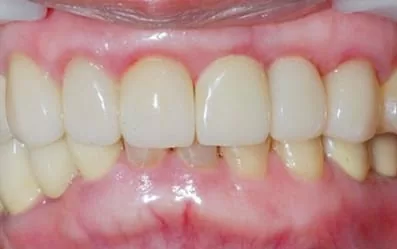

治療後:微創立即植牙恢復美麗外觀

待牙齦塑形一個月後,接上客製化氧化鋯柱心。

製作全瓷冠,是不是完全看不出來曾經接受2顆植牙呢!

比較最初與植牙後的X片,可見到左邊與自然牙間完整保留原來的骨質(水平線),右邊與植牙間更誘導再生出更多的骨質(箭號),如此牙齦不會萎縮,才能塑型到漂亮。